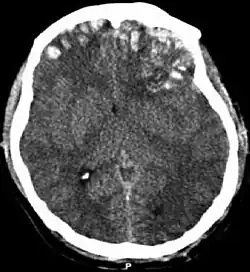

![]() Kontuze na CT snímku se subdurálním krvácením a frakturami | |

Pohmoždění mozku (latinsky: contusio cerebri, mozková kontuze) je nepenetrující poranění hlavy a mozku. Působící mechanická síla má vyšší intenzitu než v případě otřesu. Současně zde působí mechanizmus "coup" i " contrecoup" (viz otřes).

V mozkové tkáni jsou patrné na rozdíl od komoce významné mikroskopické i makroskopické patologické změny, včetně krvácení.